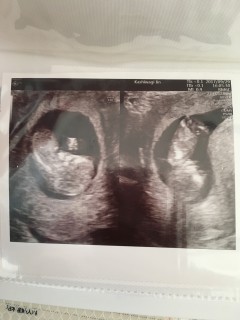

12w1dの時の写真です。上に三人姉妹が居ます。産み分けをもろもろ試し妊娠した子です。性別は7、8割り男の子と言われました!色んな角度から突起の確認をしてもらい、血流も確認してもらい(笑)念願の男の子です。令和元年ベビー、大切に育てていきます。

今回、パパと一緒にエコーみたらなんと性別まで分かっちゃいました(笑) 立派なものが生えてましたね。 スクスクと育ってくれてよかった(*´ω`*) 悪阻が酷いけどエコーを見ると頑張れます!

1ヶ月ぶりの検診。 経腹エコー。4D(*^^*) たくさん動いてくれてたし 手で頭触っててすごく可愛かった。 顔見れなかったのは残念やった(-_-;) 次も1ヶ月後!すくすく育ってね! CRL69.3